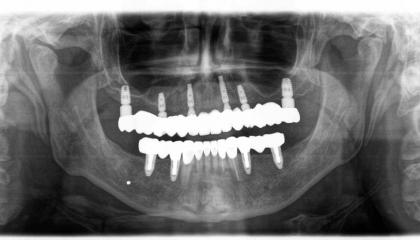

Zirconia bridge on Southern DC Implants

After